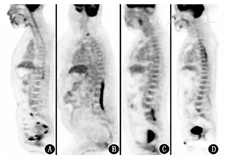

患者因颅内病变待查行18F-脱氧葡萄糖(fluorodeoxyglucose, FDG)PET/CT显像,结果示右侧颞叶前内侧、右侧岛叶、右侧壳核及尾状核头区代谢增高[最大标准摄取值(maximum standardized uptake value, SUVmax)18.3],右侧壳核及尾状核头明显肿胀,右侧侧脑室受压变窄,右侧小脑半球代谢较对侧减低;另外下丘脑、颅底多组颅神经根亦可见代谢增高,包括双侧动眼神经、三叉神经、听神经根(图1)。PET/CT躯干显像见C2~7、T11~L1水平椎管内脊髓代谢节段性增高(SUVmax 5.2),其余脏器未见明显代谢增高病灶(图2)。从定位诊断来看,听力下降定位于听神经、内侧膝状体、听辐射或颞横回;视力下降定位于视神经;肢体震颤定位于锥体外系;嗜睡定位于间脑;癫发作定位于大脑皮质;言语混乱、谵妄等精神行为异常定位于边缘系统;小便障碍定位于骶髓或马尾。患者的这些临床症状与PET/CT发现的异常代谢基本吻合。

PET/CT的脑代谢异常比较受关注,但脊髓的代谢情况有时会被忽略。正常的脊髓可以有轻度的代谢增高,并且代谢分布不均匀。正常人的脊髓FDG摄取从延髓向下呈逐渐下降趋势,通常在C4~7、T11~L1节段的脊髓FDG代谢会比其他节段更高(如图3A),这与脊髓相应的解剖位置有关:C4~T1椎体水平脊髓(脊髓节段C4~T1)及T11~L1椎体水平脊髓(脊髓节段L4~S1)分别是颈膨大及腰骶膨大所在部位,主要发出支配上下肢的脊神经,该节段脊髓相对于其他部位脊髓有更多的神经纤维交叉,灰质成分相对多,神经传导功能较其他部位相对活跃[1,2,3,4]。本例患者脊髓的代谢增高区与脊髓生理性摄取增高的部位较为相似,但范围更大(C2~7、T11~L1),代谢增高更明显(摄取已明显高于肝脏),并且代谢更不均匀,加之患者有四肢活动、尿失禁方面的症状,所以本例患者脊髓的代谢增高是病理性的。

导致脊髓代谢增高的疾病有很多,如脊髓原发肿瘤、转移瘤、血液系统肿瘤、感染性疾病、免疫性炎性疾病、创伤或者局部治疗(如化疗、放疗、手术)后等,表现为脊髓不同节段、不同程度的代谢增高。受PET分辨率的限制,难以更精确地定位病变是位于脊髓、柔脊膜、或硬脊膜,需要辅助MRI,不同的定位可能有助于进一步鉴别诊断。就脊髓病变本身而言,若全身没有其他部位或脏器受累,只依靠PET/CT很难鉴别。图3B所示为1例淋巴瘤患者,主诉双下肢无力伴远端肢体麻木,肌电图提示双下肢神经源性损害,多次腰椎穿刺提示淋巴细胞性炎性反应,EB病毒(Epstein-Barr virus, EBV)的DNA为1 800拷贝/ml,激素及抗病毒治疗有效,但随后在治疗期间症状加重,PET/CT见T12~L4椎体水平脊髓肿胀,代谢异常增高,考虑淋巴瘤可能,最终患者确诊为脊髓弥漫性大B细胞淋巴瘤。

脊髓转移瘤也可表现为脊髓节段性代谢增高,主要见于肺癌、乳腺癌、肾细胞癌、黑色素瘤等,一般有明确病史,通常发生脊髓转移时肿瘤已全身广泛转移,PET/CT诊断相对容易。图3C所示为1例卵巢癌脊髓转移的患者,患者数年前行卵巢癌肿瘤细胞减灭术及多程化疗,3年前出现小脑转移,行多次手术切除及放疗,近1个月出现下肢活动不利、言语不清,PET/CT发现小脑术区复发,同时发现腰椎下段水平椎管内脊髓肿胀,代谢异常增高,考虑脊髓转移。而本例患者的颅内病变与实体瘤脑转移的表现不同,脑转移一般为类圆形实性或囊实性病灶,界限清晰,坏死、出血明显,周围水肿明显,占位效应显著。

感染性疾病同样可导致脊髓、脑代谢异常,包括病毒感染、各种细菌感染等。病毒性脑炎发病较快,早期以水肿为主要表现,CT急性期早期可表现正常或脑实质密度改变,MRI通常可见弥漫或者局限的长T1长T2信号,脑回肿胀,脑沟变浅,亚急性期以后由于血-脑屏障受损,可见斑片状强化。最常见的单纯疱疹病毒性脑炎可形成典型的"刀切"显像,即病变可从颞叶内侧面、额叶眶面延续累及扣带回、岛叶,基底节区不受累,与本例颅内病变的受累部位相反;巨细胞病毒脑炎可表现为脑室旁白质区异常信号,可累及基底节、脑干、海马等;EBV脑炎常累及基底节、丘脑,与本例的病变范围相似。病毒性脊髓炎炎性反应损伤脊髓平面以下常表现为各种功能障碍或不完全性障碍,临床表现为完全或不完全性截瘫,图3D为1例急性脊髓炎患者,其胸段脊髓代谢不均匀异常增高。本例患者既往有肺结核病史,还需鉴别中枢神经系统结核感染。中枢神经系统结核一般表现为结核性脑膜炎、颅内结核性肉芽肿、椎管内结核性蛛网膜炎,CT和MRI可发现蛛网膜炎、脑水肿、脑梗死、结核性肉芽肿等,脊髓受累时可见脊髓代谢弥漫不均匀增高,而本例颅内病变表现与结核性脑膜炎、结核性肉芽肿明显不同。